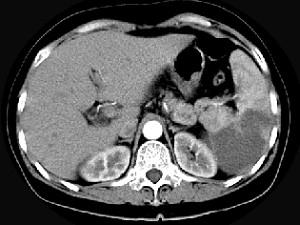

女、54岁,左上腹痛,CT检查如图,最可能的诊断是 ( )A、脾血管瘤B、脾转移瘤C、脾脓肿D、脾梗死E、脾淋巴瘤

问题 女、54岁,左上腹痛,CT检查如图,最可能的诊断是 ( )

选项 A、脾血管瘤 B、脾转移瘤 C、脾脓肿 D、脾梗死 E、脾淋巴瘤

答案 D